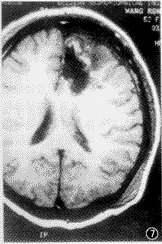

三、术区积血或渗血

图7,8 患者 女,52岁。左额间变性星形细胞瘤术后20h。平扫可见术区周边有少量积血,表明有正铁血红蛋白的早期形成(图7)。注药后可见术区附近脑膜增强(图8)